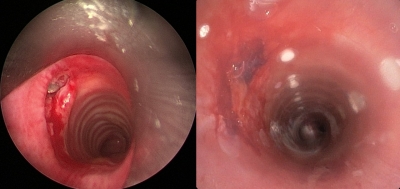

The bullet had entered from lower back and entered the chest and was lodged within the airway wall. Because of this, air leaked out in the surrounding area leading to difficulty in breathing.

After an initial bronchoscopic assessment, rigid bronchoscopy was performed through mouth under general anaesthesia and bullet was removed using rigid forceps by Dr Amit Kumar Singh of Department of Trauma Surgery.

Thereafter, a silicone stent was placed to cover the rent of approximately 2 cm in the airway wall.